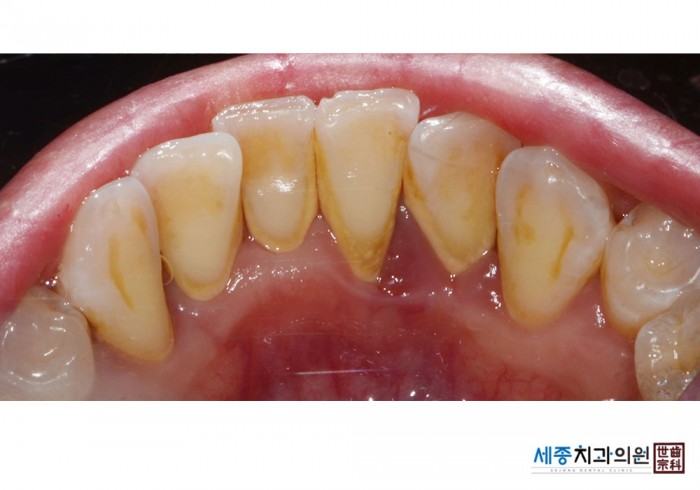

[스케일링] 치주질환 예방 스케일링

치료전 : 2020-09-18

가글마취&저주파 스켈러를 사용한 착색제거 스케일링